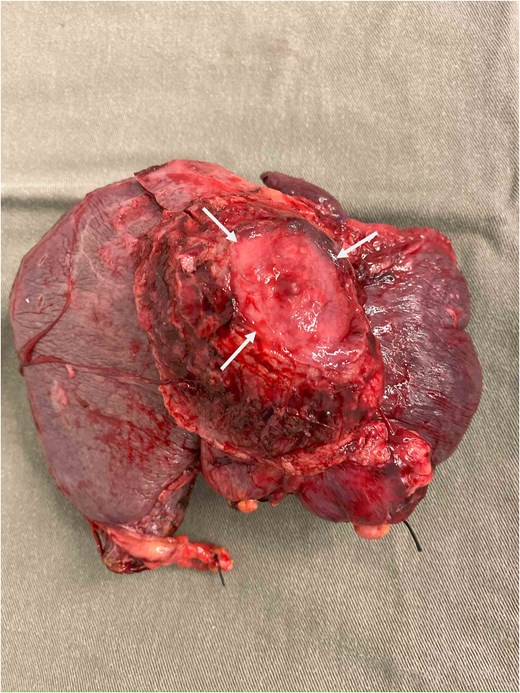

During operation, an exophytic 7 cm segment 4 tumor was found invading superiorly to left hemidiaphragm and pericardium, inferiorly invading to first part of duodenum. A cuff of duodenal wall was removed with tumor and the duodenal defect was closed primarily with 3/0 PDS. Part of the left hemidiaphragm together with pericardium was resected, the heart and left lung were exposed (Fig. 3). The diaphragmatic/pericardial defect was closed with Gore-Tex mesh with single layer continuous 3/0 Prolene (Fig. 4). Air was expelled through an under-water seal catheter placed in the pleural cavity before suture was tightened and tied. Left trisectionectomy was then completed (Fig. 5). The patient developed intra-abdominal collection after surgery which resolved with percutaneous drainage. Pathology confirmed a 7 cm ICC, there was evidence of rupture with abscess formation, and adhesion but no direct invasion to duodenum and diaphragm (Fig. 6). The resection margin was clear. No satellite lesion or microvascular invasion. CEA decreased to normal level after surgery. The patient declined adjuvant chemotherapy.

Specimen removed, the transected liver surface was covered with applied tissue glue (arrows) and the duodenal repair site was seen (arrow heads).